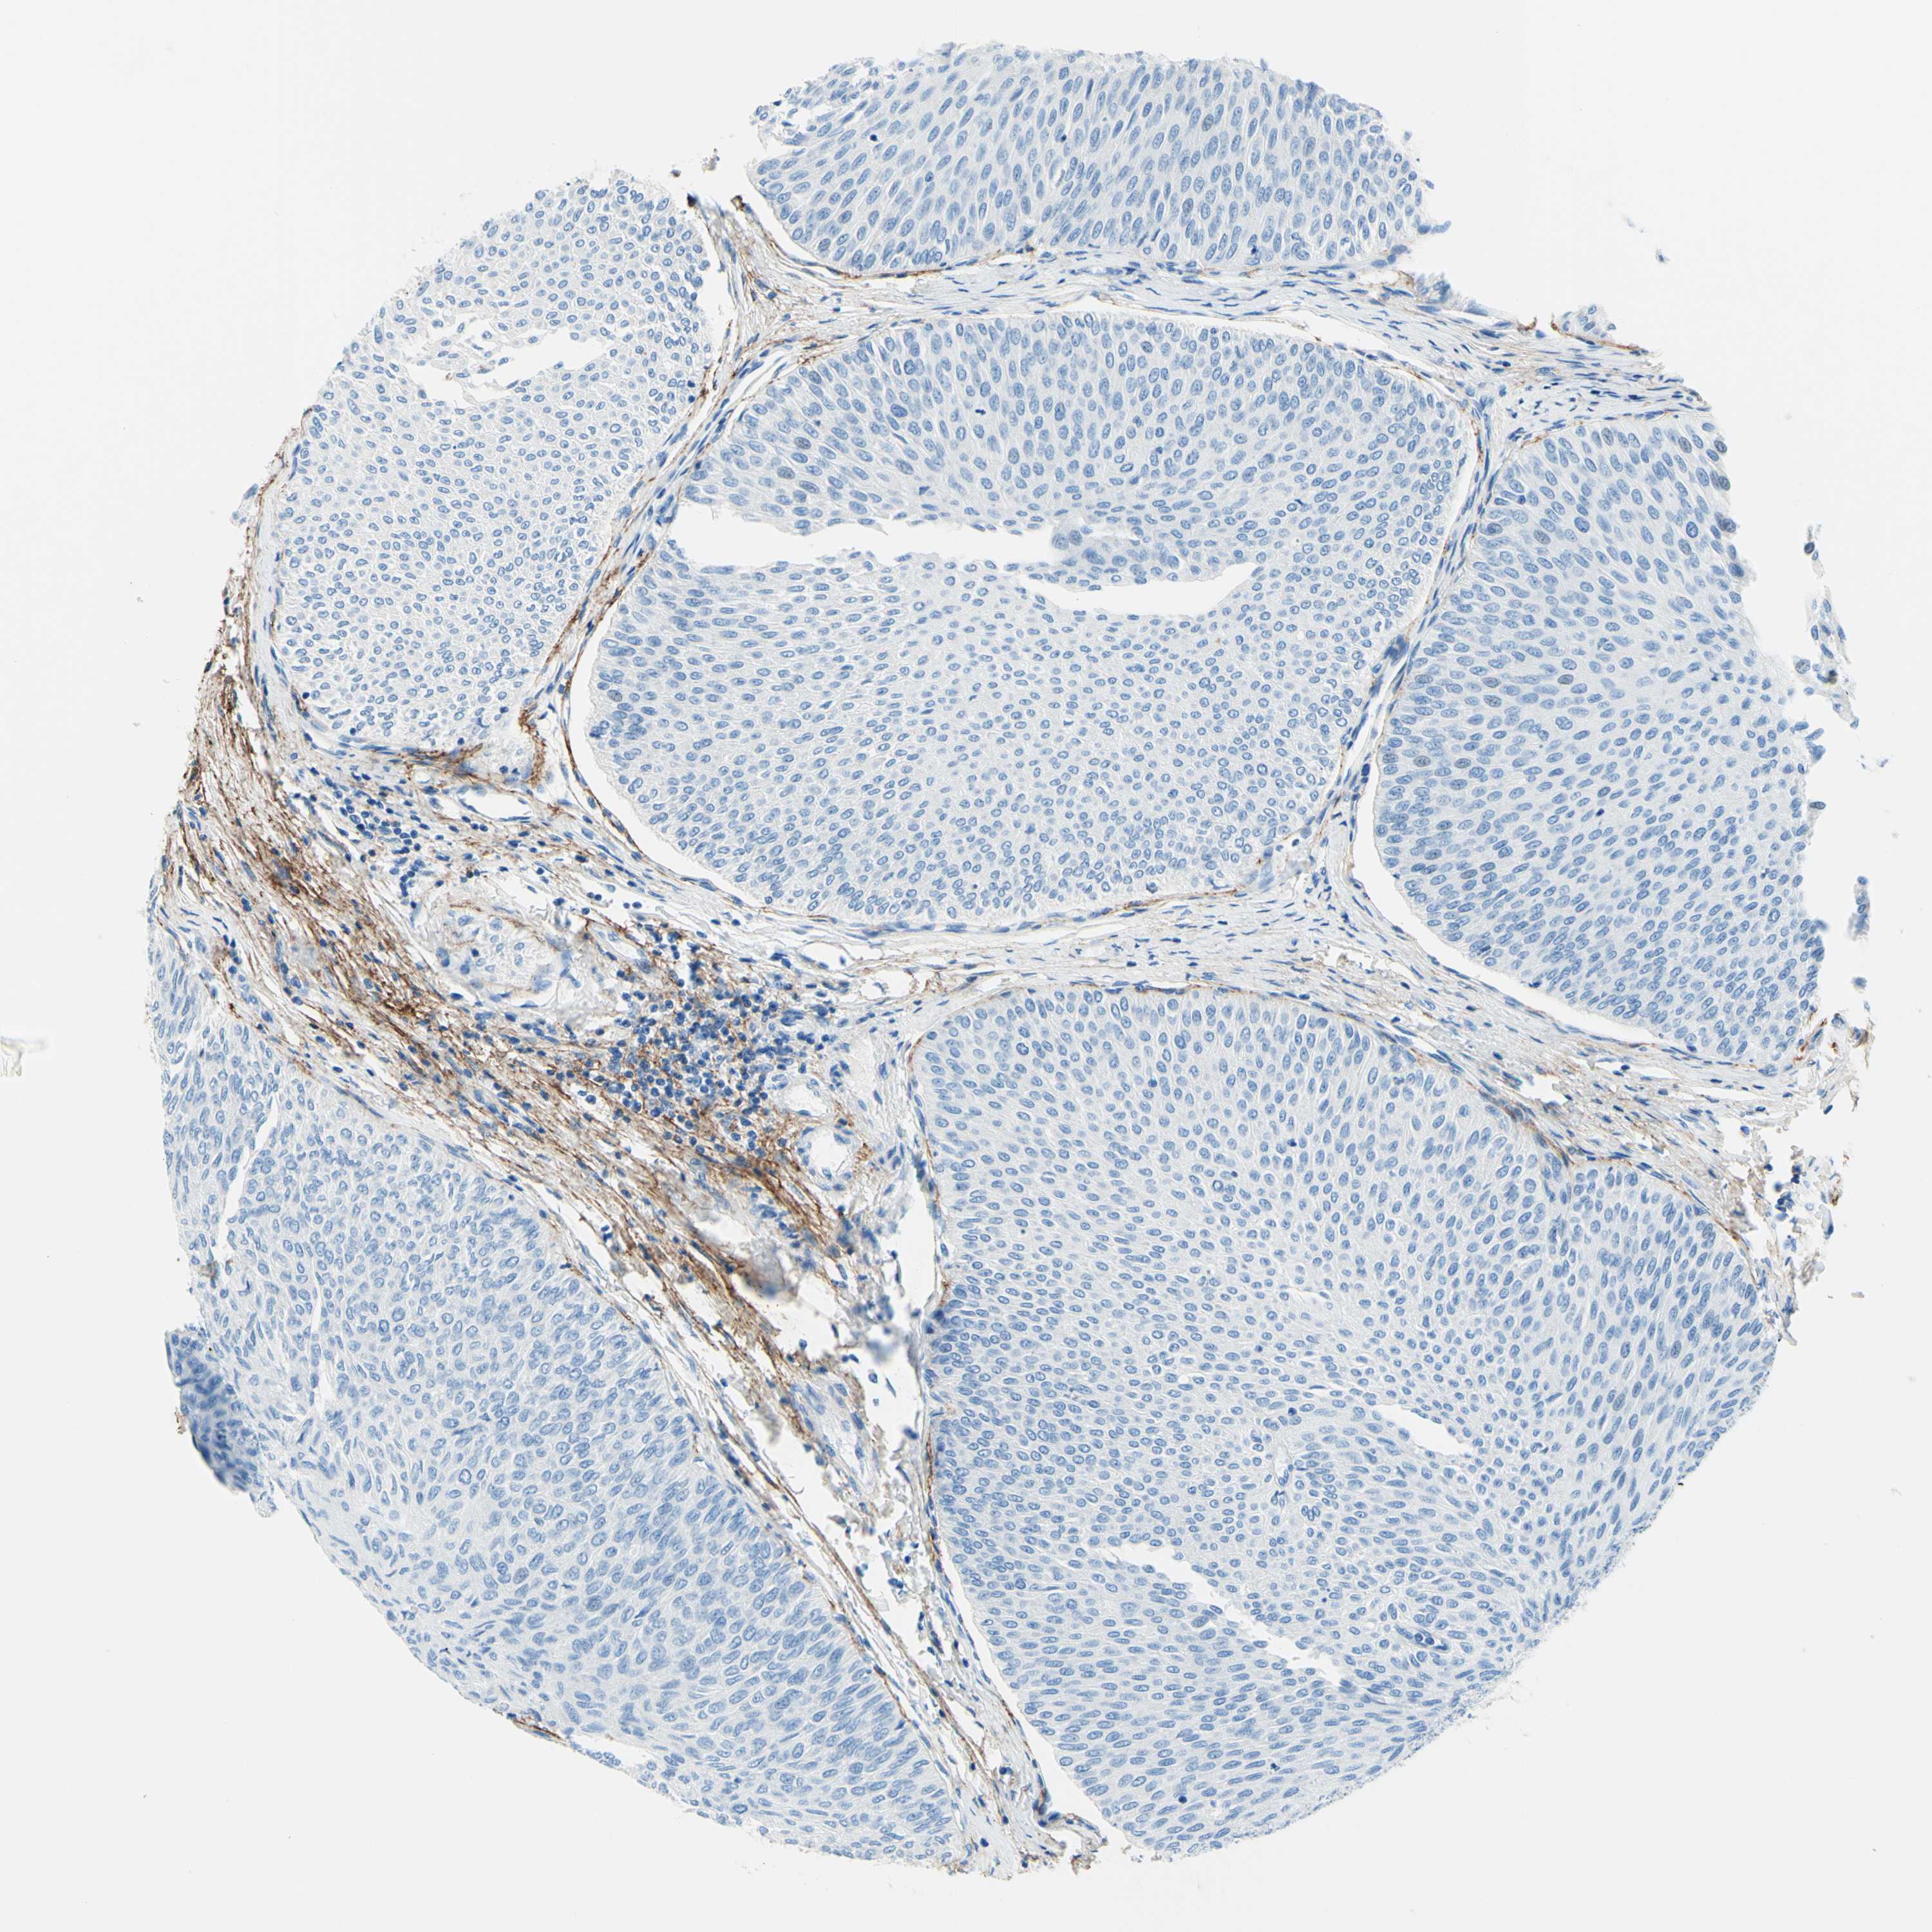

UROTHELIAL CANCER - Protein expressioni

A mouse-over function shows sample information and annotation data. Click on an image to view it in a full screen mode. Samples can be filtered based on level of antibody staining by selecting one or several of the following categories: high, medium, low and not detected. The assay and annotation is described here.

Note that samples used for immunohistochemistry by the Human Protein Atlas do not correspond to samples in the TCGA dataset.

Antibody stainingi

Antibody staining in the annotated cell types in the current human tissue is reported as not detected, low, medium, or high, based on conventional immunohistochemistry profiling in selected tissues. This score is based on the combination of the staining intensity and fraction of stained cells.

Each image is clickable and will lead to virtual microscopy that enables deeper exploration of all samples and also displays staining intensity scores, fraction scores and subcellular localization as well as patient and tissue information for each sample.

Antibody HPA010553

Staining

High

Medium

Low

Not detected

Intensity

Strong

Moderate

Weak

Negative

Quantity

>75%

75%-25%

<25%

None

Location

Nuclear

Cytoplasmic/membranous

Cytoplasmic/membranous,nuclear

Urothelial carcinoma, Low grade

Urothelial carcinoma, High grade